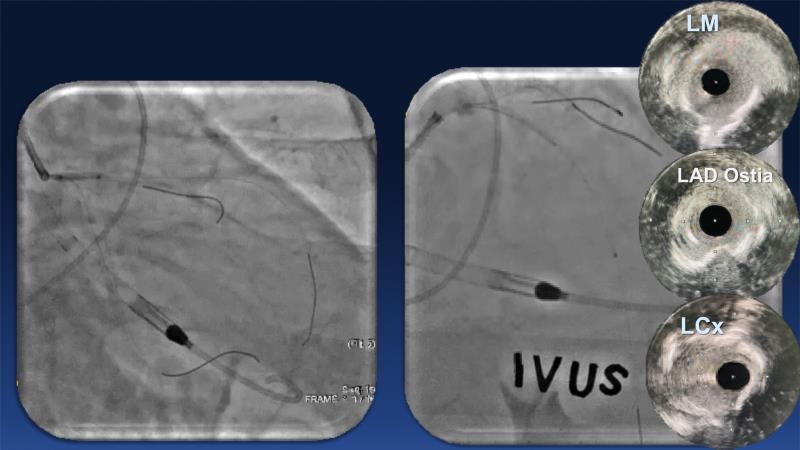

Over the last five years, we have learned that there is a new tool for treating calcium, the greatest enemy of interventional cardiology, which can take various forms: intravascular lithotripsy. In this session, look at how to master this technique in different scenarios, from eccentric calcified lesions to left main bifurcations.

- To understand the mechanism of action of intravascular lithotripsy (IVL) for the treatment of calcified lesions

- To uncover practical tips and techniques for IVL in challenging calcified lesions: eccentric calcified lesions

- To learn how to safely utilise IVL in left main bifurcations